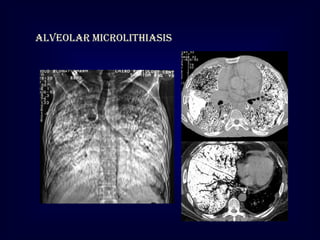

Pulmonary alveolar microlithiasis

Innumerable tiny calcific particles are diffusely distributed in the alveoli

•

Most patients are asymptomatic

Dense sharply defined nodules

The density is greatest in the lung bases

Black pleura sign [unaffected pleura

between lung and ribs]

Alveolar microlithiasis

Pulmonary alveolar microlithiasis Innumerabletiny calcific particles are diffusely distributed in the alveoli • • • • Most patients are asymptomatic Dense sharply defined nodules The density is greatest in the lung bases Black pleura sign [unaffected pleura between lung and ribs]